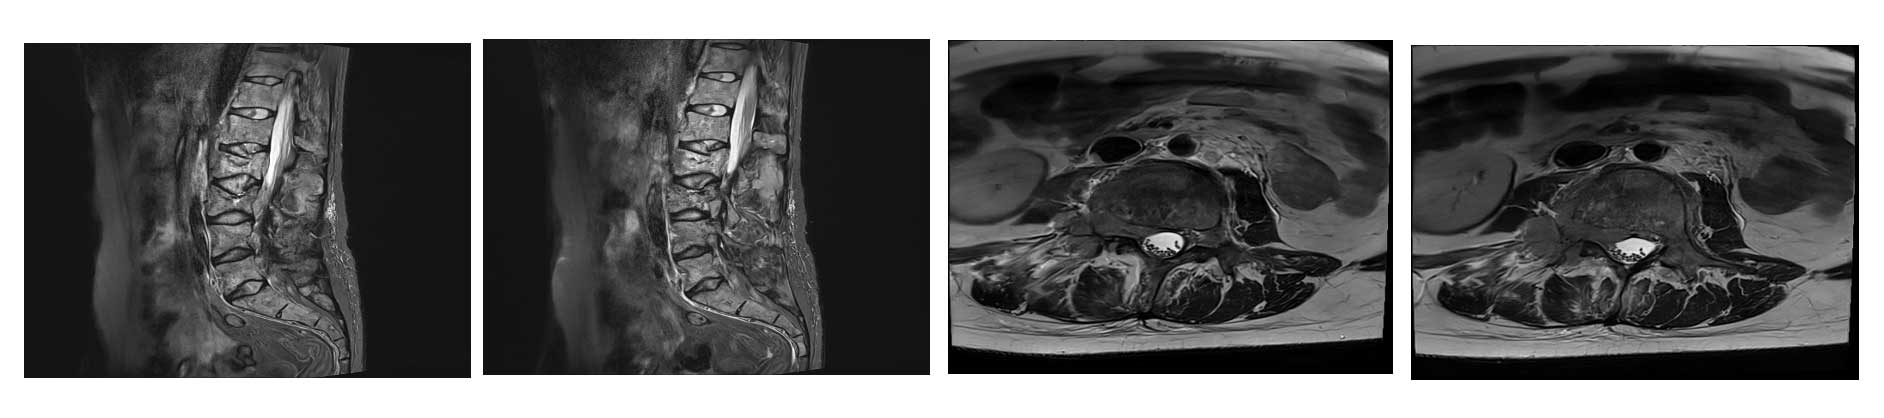

Ameliyat Öncesi: MR’da iki seviyede patolojik kırık, epidural ve kök basısı görülmekte.